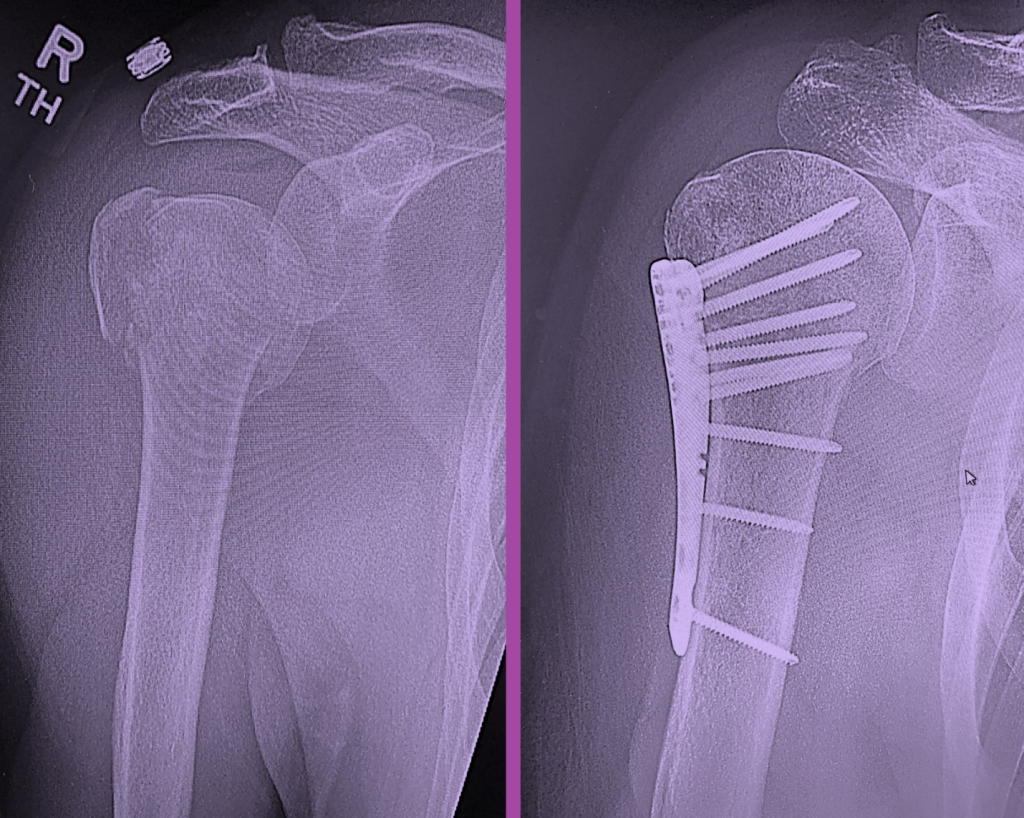

Can Humerus Fracture Heal It takes three to four months for the bone to heal. It is important to remember that a. Explore how physical therapy can be a powerful, nonsurgical solution. A humeral fracture can take weeks or months to heal, sometimes requiring surgery. During this time, you will do exercises to get better. Surgery usually involves fixation of the fracture fragments with plates, screws or pins. What is a proximal humerus fracture? It takes three to four months for the bone to heal. See your orthopedic specialist for proper diagnosis and treatment. Humerus fractures might seem severe, but you can heal a humerus fracture without surgery. What to do if i am struggling? A fracture of the proximal part means that it is broken up near the shoulder joint. The humerus is the long bone in your upper arm. Most broken shoulders can be treated without surgery.

Fracture of humerus successfully fixed by Dr.Tusha Can Humerus Fracture Heal See your orthopedic specialist for proper diagnosis and treatment. What is a proximal humerus fracture? A fracture of the proximal part means that it is broken up near the shoulder joint. Humerus fractures might seem severe, but you can heal a humerus fracture without surgery. Most broken shoulders can be treated without surgery. It takes three to four months for. Can Humerus Fracture Heal.